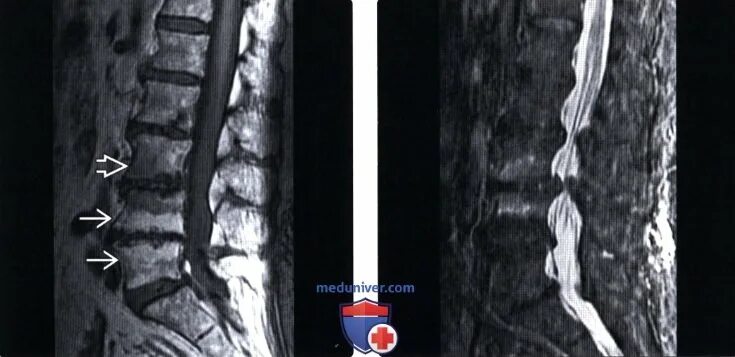

Дегенеративные изменения диска l5 s1